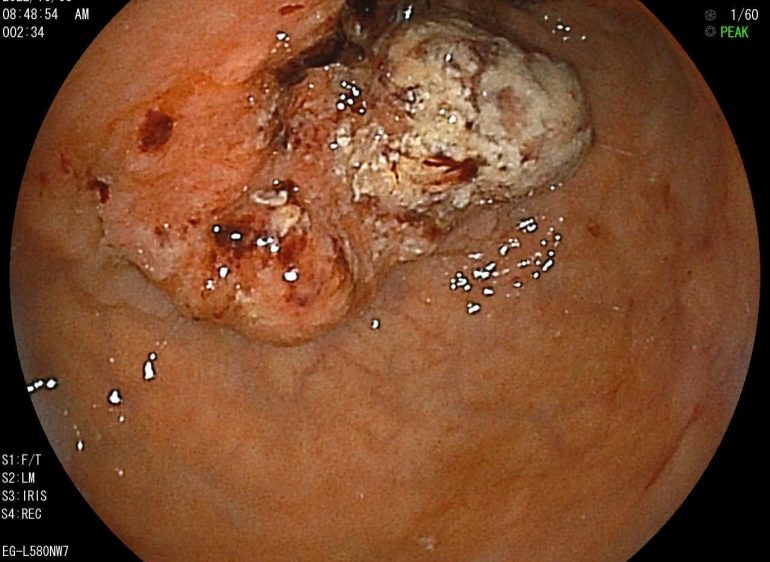

これまで当院で内視鏡検査を受けていただいた方々の症例紹介です。

当院では、下記の画像にあるような消化器疾患に対して質の高い内視鏡検査をご提供しています。

【進行胃がん】

健康診断・地域検診で広く行われているバリウム検査(胃X線検査)のみでは、早期がん発見は困難であるため、検査を受けてみると進行してしまっていたというケースもあります。

進行度に比例して死亡率も高まってしまうので、胃カメラ検査による早期発見を心がけましょう。